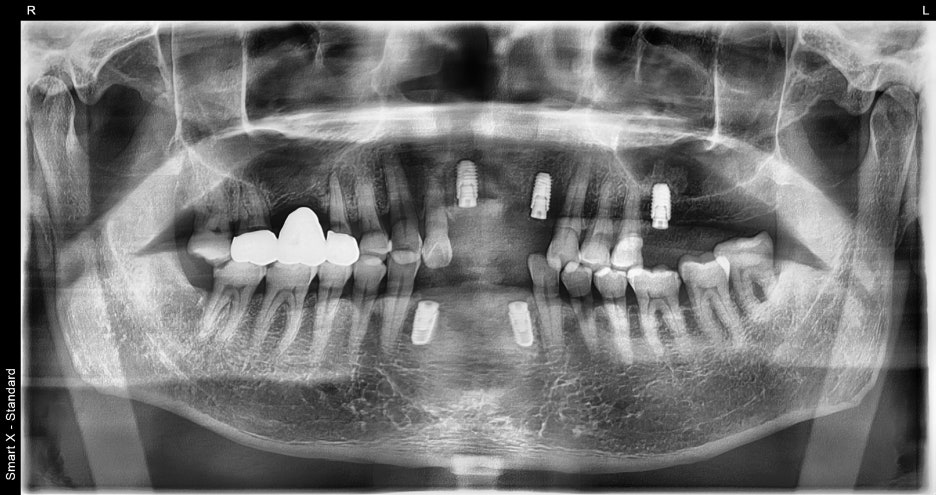

③ 임플란트 식립 (총 5개)

– 여러 부위에 5개의 임플란트를 심었습니다.

– 일부 부위는 뼈 두께가 부족해

뼈이식(동종골 이식)을 병행했습니다.

– 디지털 장비를 통해 정확한 위치와 각도로 식립하여

심미성과 기능을 동시에 확보했습니다.